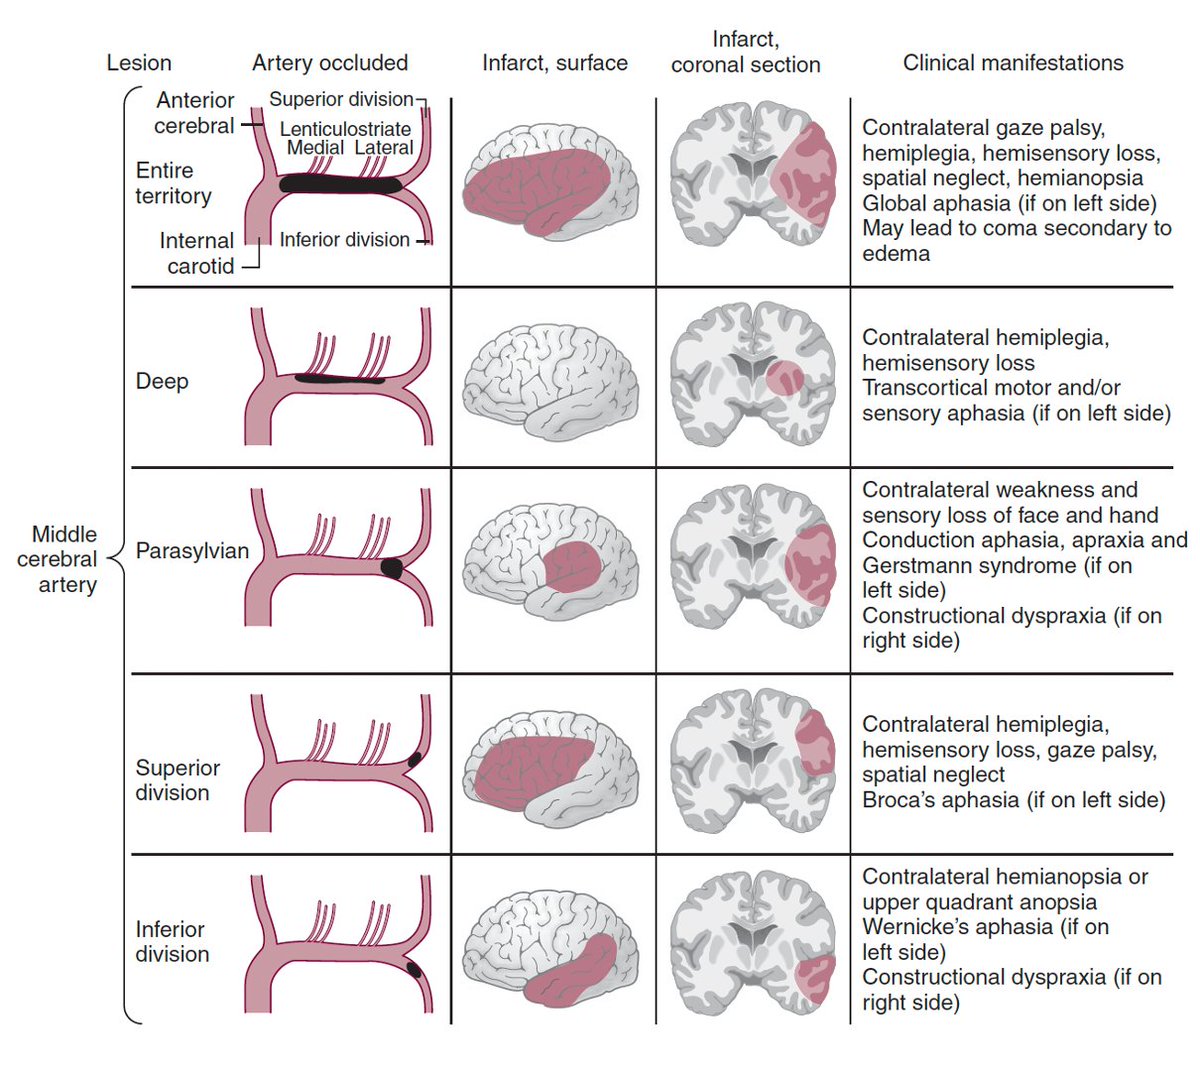

⭕️MCA occlusions / 🧠 infarct patterns Maybe time for this👇again Andrew Micieli? #MedTwitter #MedStudentTwitter #MedEd #FOAMed #neurotwitter #Neurology #stroke #Neurosurgery #EndNeurophobia #FOAMrad #NeuroRad #neuroradiology #radiology #radres #RadEd #FOAMncc #MRI